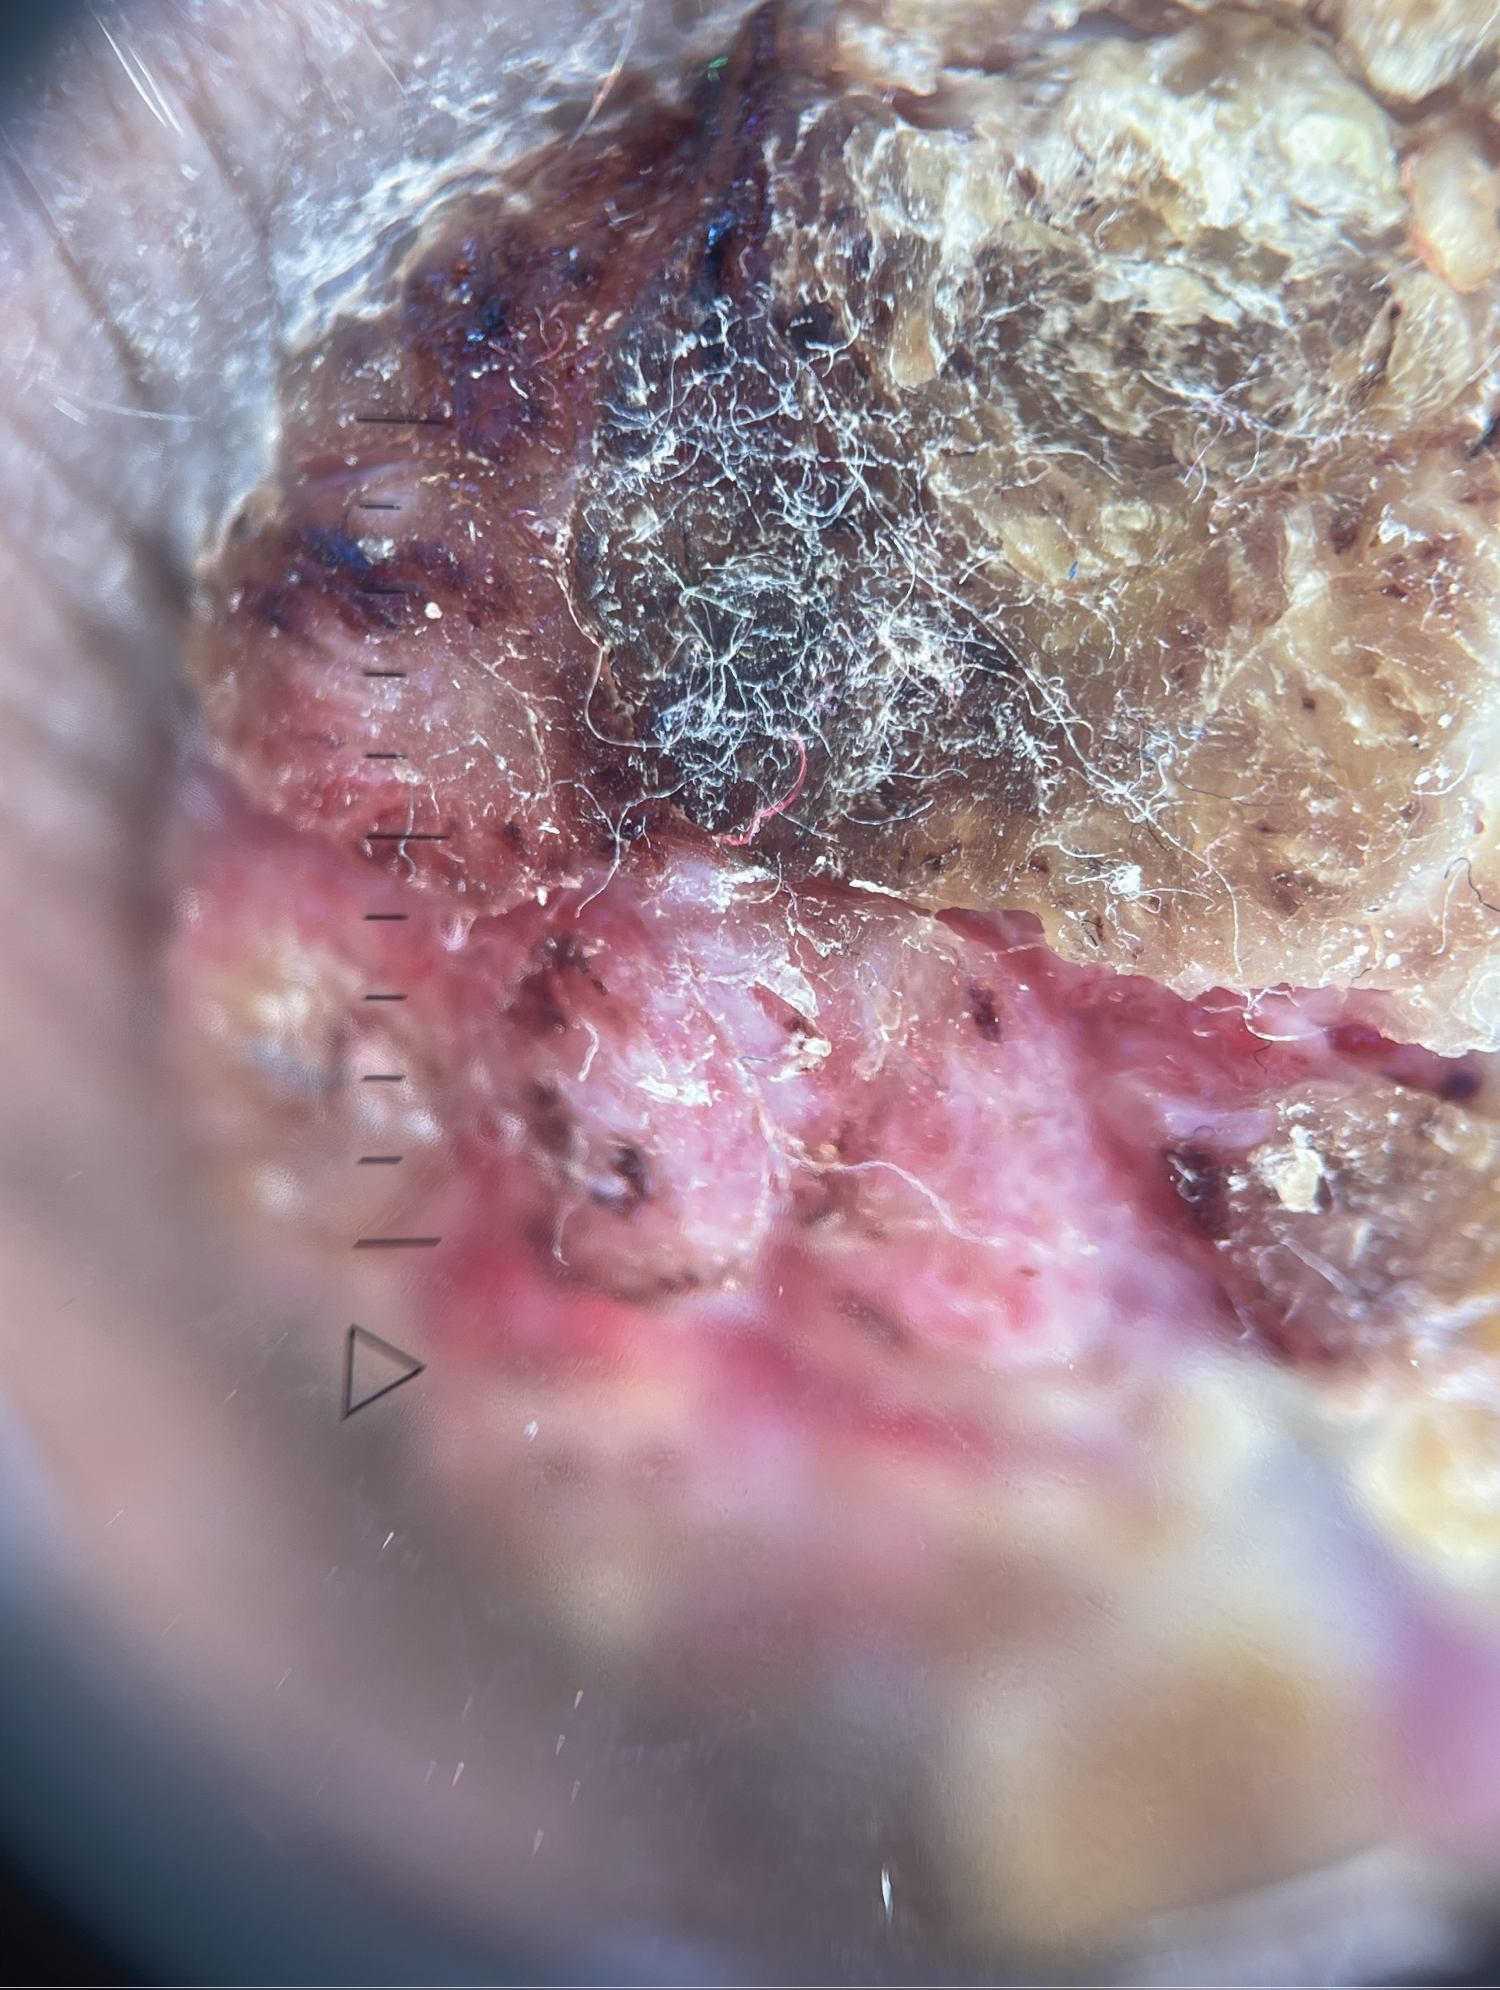

Dermatological examination revealed an exophytic lesion with a verrucous surface bleeding on contact and measuring 4 cm, associated with a painless, mobile homolateral adenopathy.

A skin biopsy revealed a verrucous tumoral lesion with extensive keratin strata composed of basophilic cells showing cytonuclear abnormalities associated with a fibroinflammatory reaction of the stroma, indicating verrucous squamous cell carcinoma. A complete excision was then performed (Figure 1 and Figure 2).

Figure 1: Exophytic tumor with a verrucous surface.

Figure 2: Dermoscopy of verrucous carcinoma.